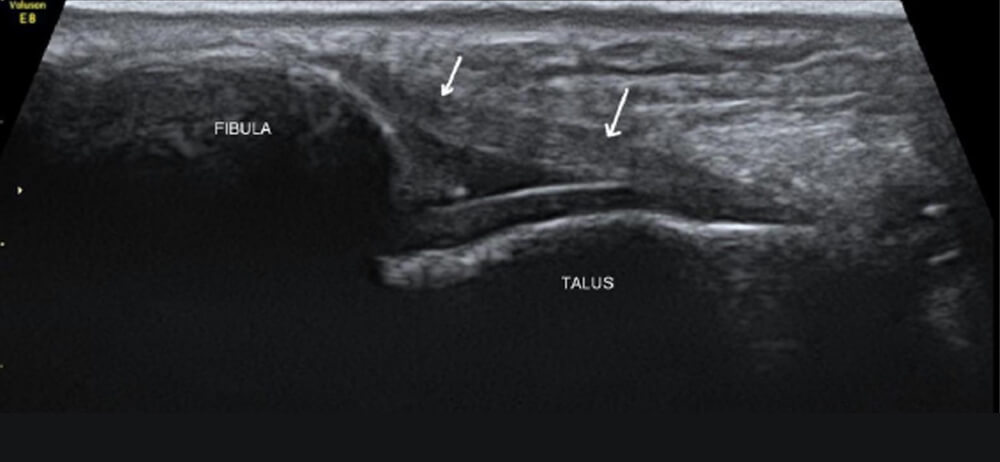

• エコーで靱帯の連続性や不安定性を確認します

エコー